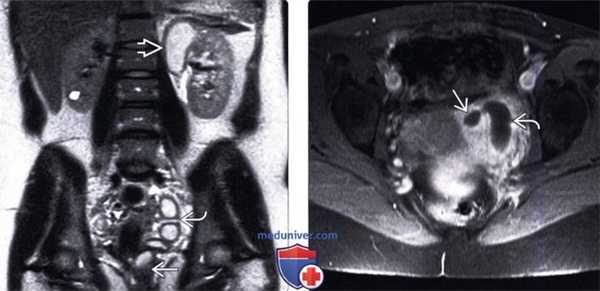

(Левый) На фронтальном Т2 HASTE МР-изображении лучше визуализируется удвоенная левая почка с окклюзированной атрофированной верхней лоханкой. Расширенный извитой мочеточник впадает во влагалище. Мочеточник утолщен в результате инфекционного процесса.

(Правый) На аксиальном Т1 FS снимке с контрастированием визуализируется эктопическое впадение левого верхнего мочеточника во влагалище. Усиление сигнала от стенки мочеточника и окружающих тканей обусловлено развитием инфекции.

(Левый) На продольном ультразвуковом срезе удвоенной левой почки визуализируются диспластические кистозные изменения верхней лоханки.

(Правый) На поперечном ультразвуком срезе мочевого пузыря визуализируется расширенный левый мочеточник, который отходит от удвоенной левой почки, и прикрепляется с образованием крупного уретероцеле.

(Левый) На трансвагинальном ультразвуковом срезе визуализируется толстостенный инфицированный мочеточник со взвесью в просвете рядом с неизмененным левым яичником. Его можно ошибочно принять за пиосальпинкс, однако строение и ход мочеточника отличаются.

(Правый) На фронтальном Т2 HASTE МР-срезе визуализируется расширенный левый мочеточник, впадающий во влагалище ниже шейки мочевого пузыря. Верхняя лоханка удвоенной системы значительно расширена. Мочевой пузырь не изменен.